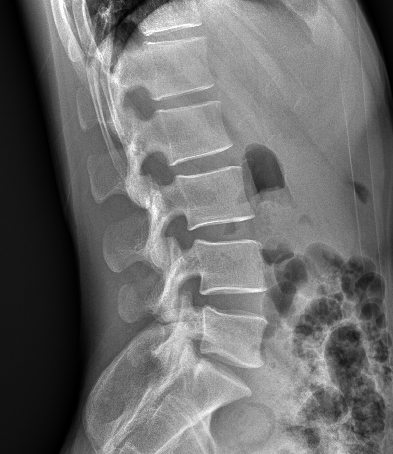

卓越的影像鏈配置是獲得優(yōu)質(zhì)影像的有力保障:普利德車載DR采用高頻高壓發(fā)生器、大熱容量球管確保穩(wěn)定、精確的射線輸出;17X17英寸大尺寸無(wú)線平板探測(cè)器,更大的視野范圍,更高的靜態(tài)空間分辨率,確保呈現(xiàn)清晰影像。

普利德車載DR可進(jìn)行胸部等部位的X射線數(shù)字?jǐn)z影檢查,滿足大規(guī)模體檢及傳染疾病控制需求,尤其在重大疫情預(yù)防等應(yīng)急檢查工作中具有突出優(yōu)勢(shì),為各級(jí)醫(yī)療機(jī)構(gòu)快速應(yīng)對(duì)突發(fā)性公共衛(wèi)生事件提供強(qiáng)大助力,實(shí)力護(hù)航健康之路。